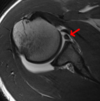

Qué es la lesión de Bankart

Desgarro del labrum glenoideo anterior en la luxación humeral

Lesión de Bankart y está relacionado con la inestabilidad de hombro o luxación recidivante.